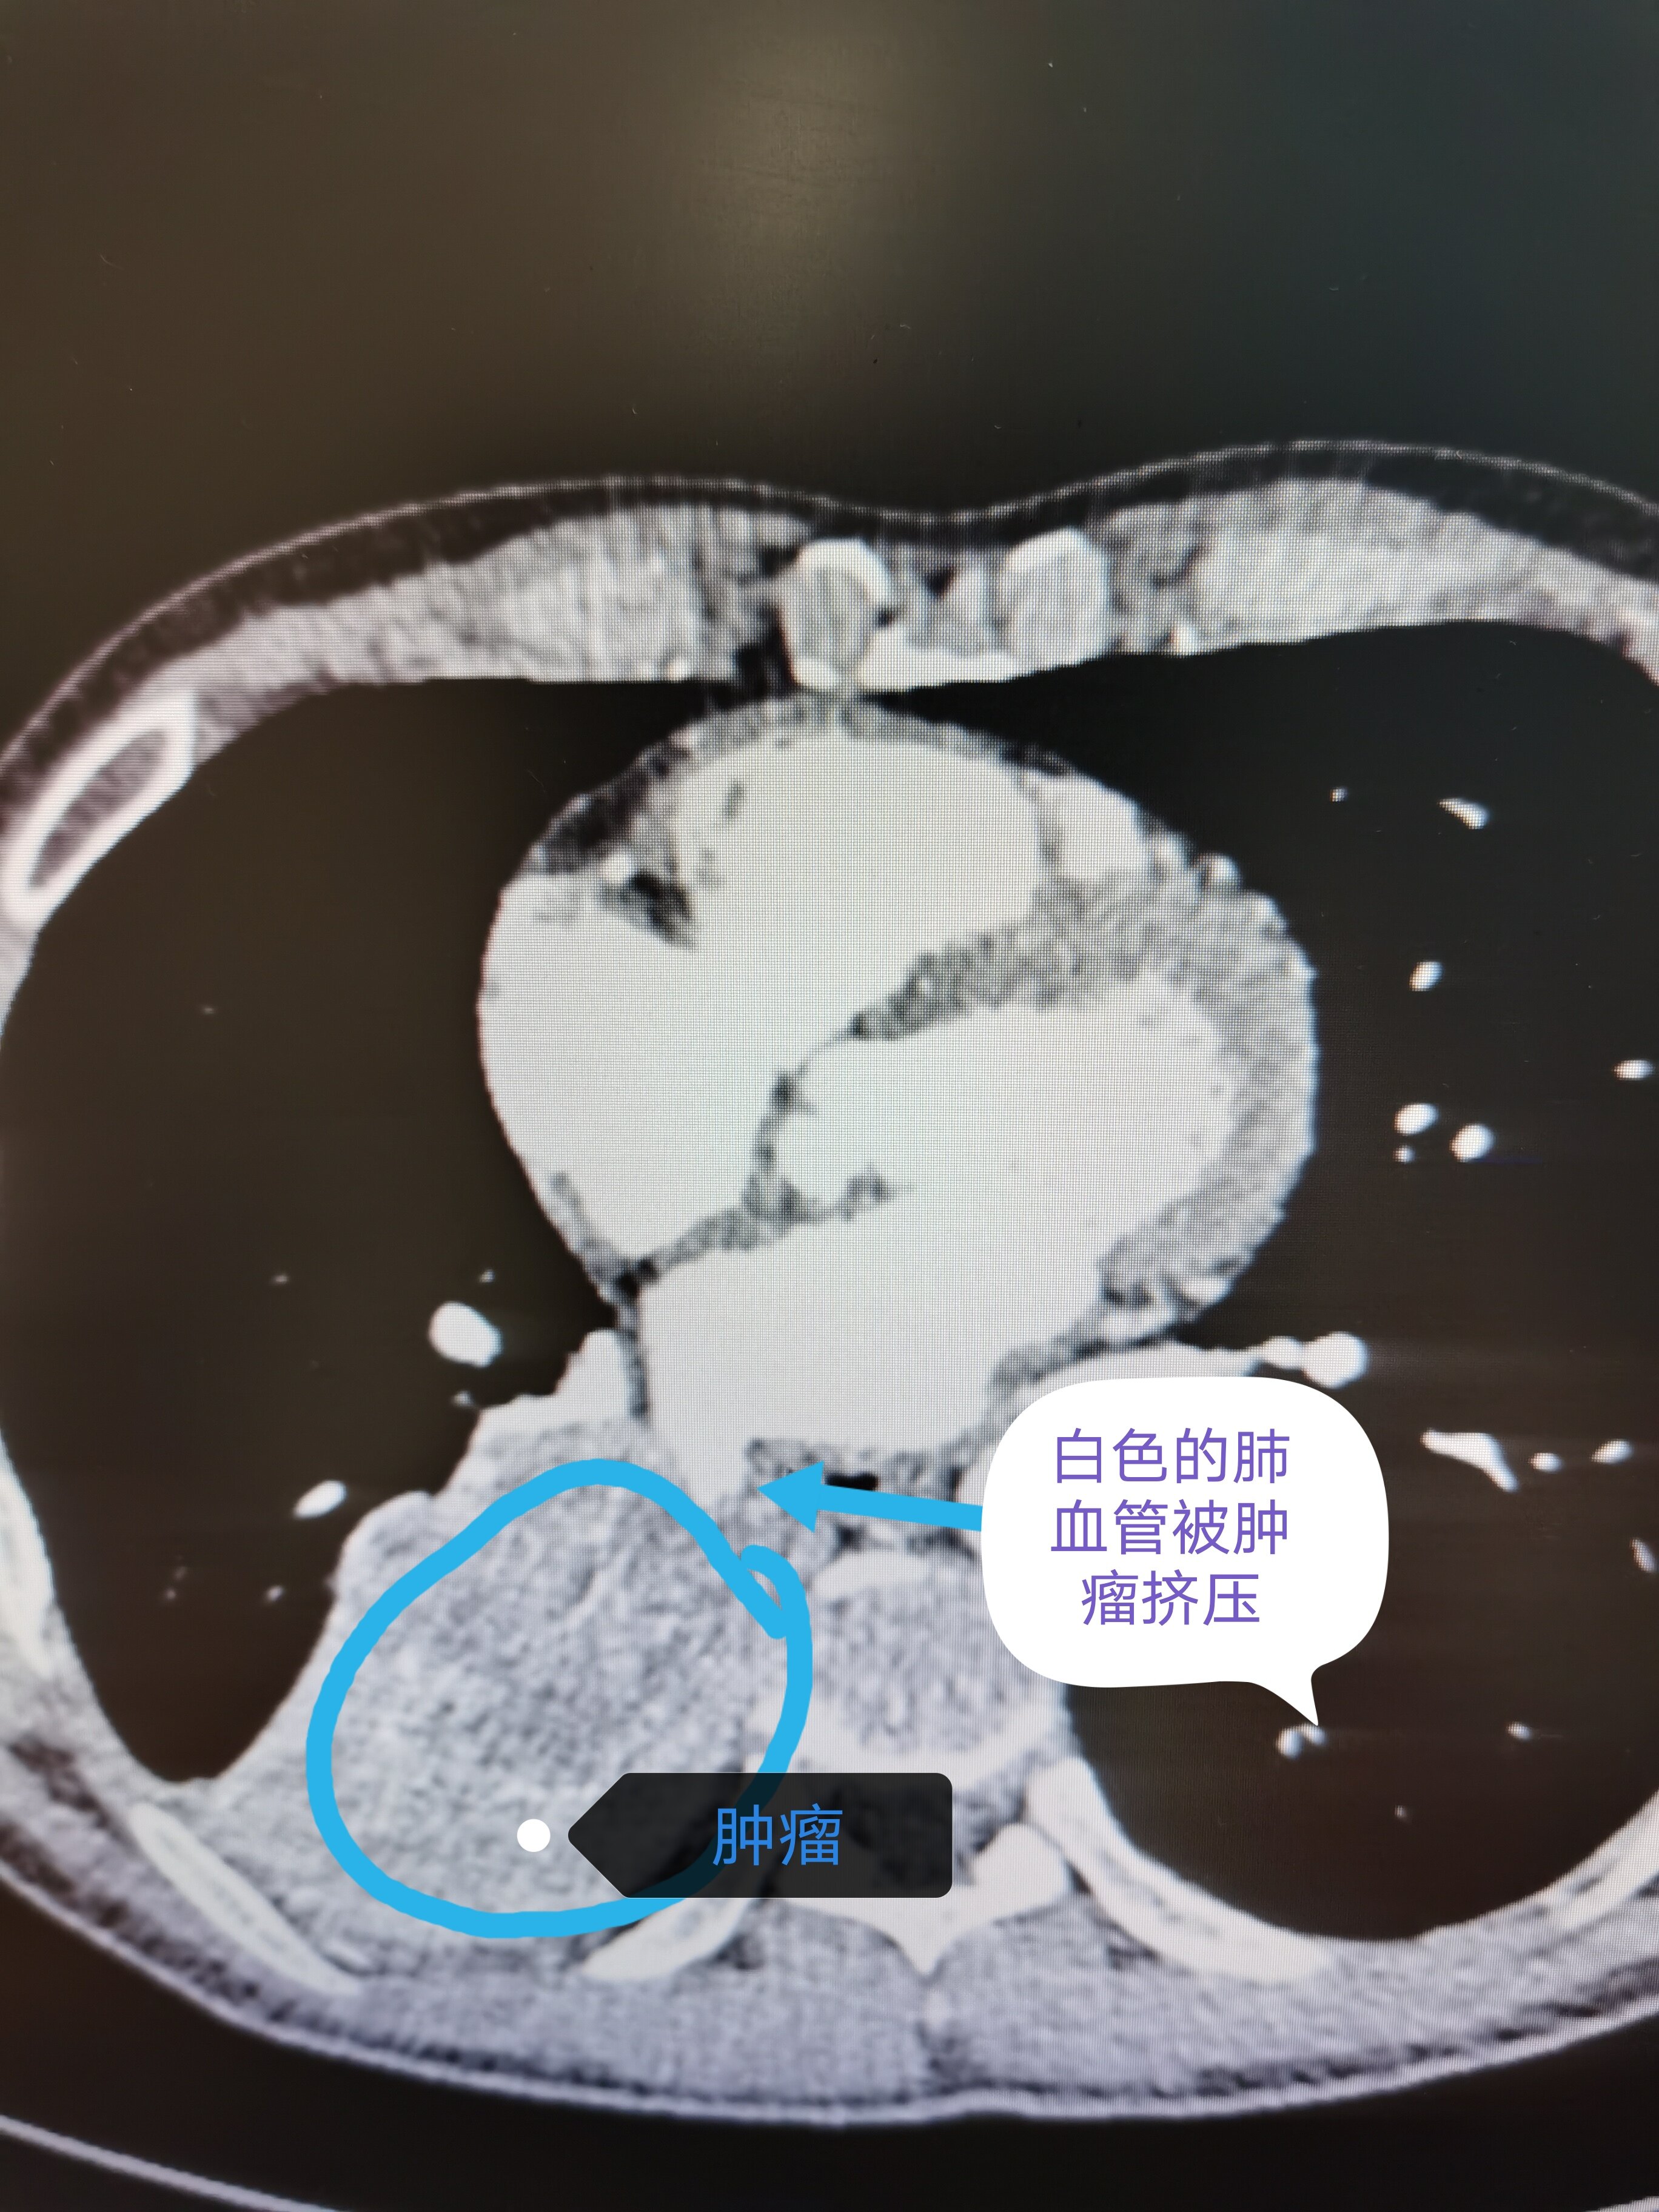

当肿瘤巨大,侵犯主要气管或者侵犯大血管时,并非一定不可以手术,而是可以通过心包内处理血管,这样更加安全避免血管大出血,侵犯气管主干是可以通过气管切除后,再行健康支气管修剪后原位移植,可以保留健康肺组织,避免全肺切除带来的风险和损失。这是我科最近手术的一例典型病例,肿瘤巨大且侵犯主气管,经过切除后原位移植,术后一周后复查CT,移植右上肺愈合良好,患者顺利康复出院